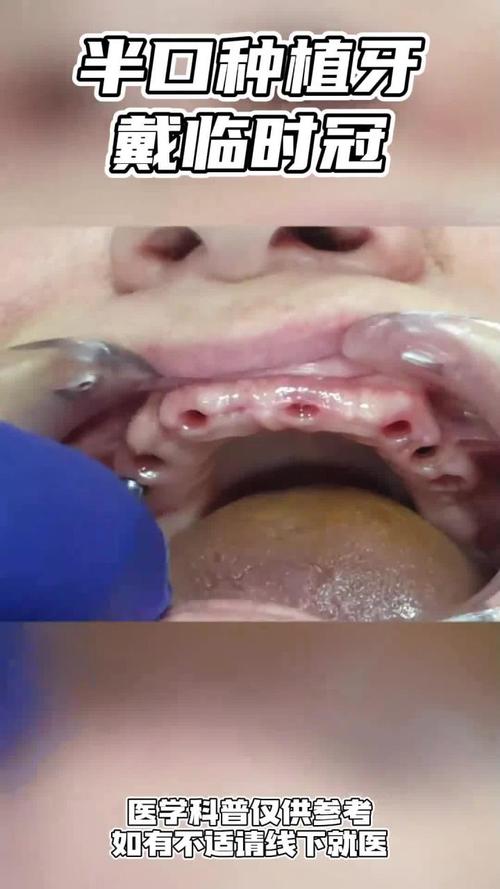

- 案例: 要求查看医生过往的种植牙案例(尤其是和你情况类似的),了解效果。